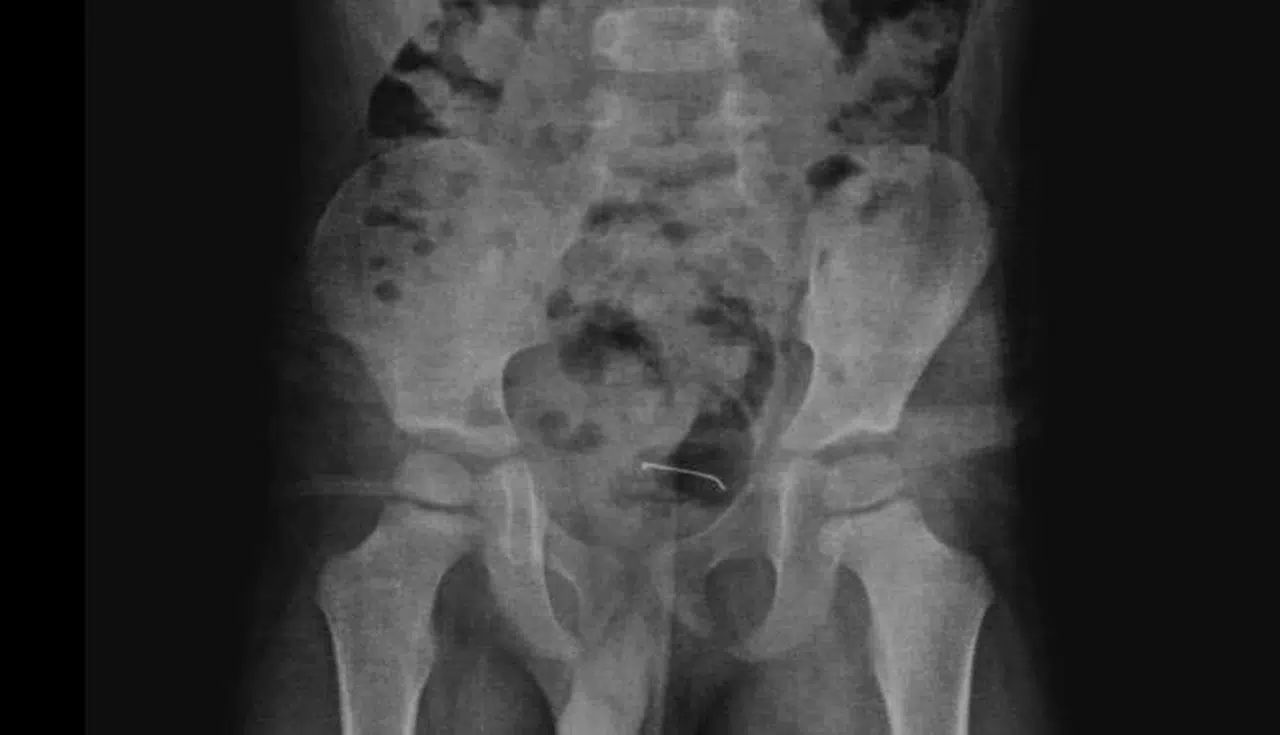

Özcan ÇİRİŞ/BİTLİS, (DHA)- BİTLİS'in Güroymak ilçesinde 5 yaşındaki çocuğun 9 ay önce yuttuğu, mesane duvarına yapışan toplu iğne, operasyonla çıkarıldı.

Güroymak'ta sürekli karın ağrısı şikayeti çeken 5 yaşındaki çocuk, ailesi tarafından çeşitli sağlık kuruluşlarına götürüldü. Sonuç alamayan aile, en son Tatvan Devlet Hastanesi'ne başvurdu. Burada çekilen röntgende, çocuğun mesane duvarında metal bir cisim olduğu belirlendi. 9 ay önce yutulan ve vücutta kalan 3 santimetrelik toplu iğnenin mesane duvarına yapıştığı tespit edilince ameliyata karar verildi.

Tatvan Devlet Hastanesi Çocuk Cerrahi Uzmanı Op. Dr. Tahsin Onat Kamçı tarafından gerçekleştirilen operasyonla, toplu iğne başarılı bir şekilde çıkarıldı. Gözlem altında tutulan çocuk, birkaç gün sonra taburcu edildi. Op. Dr. Tahsin Onat Kamçı "Cerrahi operasyonla 3 santimetre civarındaki toplu iğneyi çıkardık. Hastayı birkaç gün takipte tuttuk. Genel sağlık durumu iyi olan hastamızı taburcu ettik. Kesici ve delici cisimler çok tehlikeli. Bu gibi cisimlerin çocukların ulaşabileceği yerlere bırakılmaması gerekiyor" dedi. (DHA)